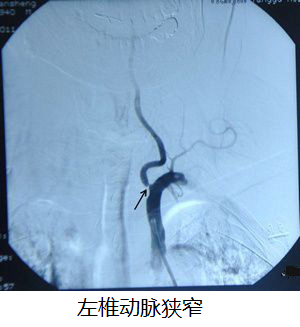

据了解,该患者因反复头晕一个月,再发加重1个半小时而由急诊收入住我院神经内科一区。头颅MRI提示脑梗塞急性期,且右侧椎动脉起始段局限性狭窄,有行全脑血管造影术及动脉支架置入术指征。

患者及其家属在详细了解手术指征及可能存在的风险后签字同意做手术。在完善各种术前准备后行全脑血管造影术,右侧椎动及左椎动脉支架成形术。手术顺利,造影见支架成形良好,原狭窄基本纠正。术后患者无头痛头晕症状,无发热,无恶心呕吐症状,生命征平稳,恢复良好,目前该患者在进一步康复中。